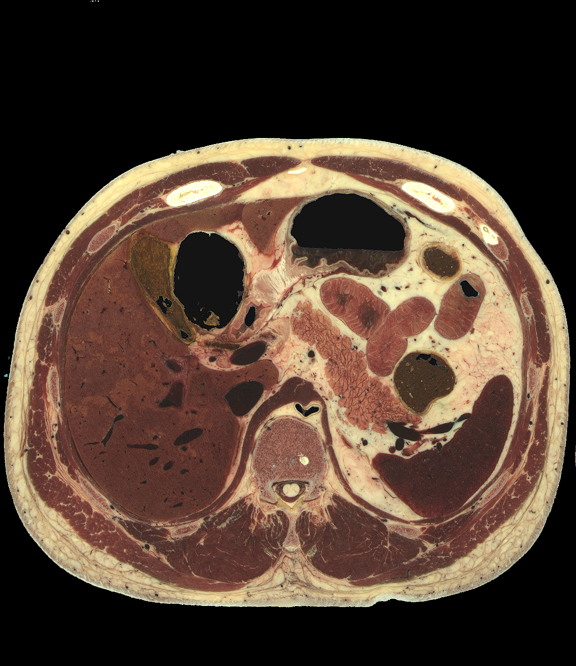

Full torso, unlabelled

Abdomen/Pelvis structures, high resolution